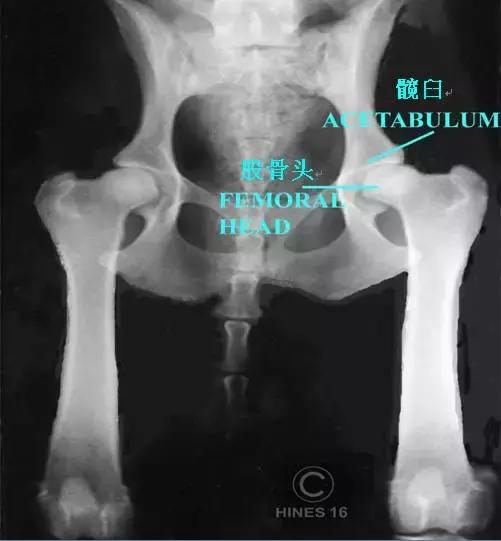

髋关节由球状的股骨头和碗状的髋臼(jiù)构成,这两个部位形成牢固的结构,使股骨头能够在髋臼中稳定地旋转(话说人也有髋关节,就是连接大腿跟躯干的关节部位)。

股骨头和髋臼之间有平滑的软骨覆盖,并有关节液使摩擦降低至最小,而且还有韧带加强支撑。

虽然触诊和观察狗的步态可以在一定程度上辅助诊断,但最准确的诊断方法是拍X光片来判断是否患有CHD。